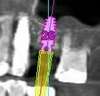

La simulation logicielle en 3D montre le projet implantaire.

L’image en 3 dimensions indique que la hauteur disponible d’os est de 7 mm

La simulation implantaire indique que la hauteur d’os à gagner est de 3 mm pour placer un implant de 10 mm